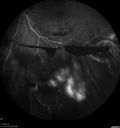

50 year old man: The patient noticed a few days ago, when putting on Contact Lenses for work which were slightly different from his usual strength. He therefore had some trouble at work with the new contact lenses. Then he had some haze in his vision. In the morning he went to see his mother in Venice and there was a new big black line in the left eye when he was getting up from lying down (this was yesterday). Then he noticed a lot of floaters in his vision that looked like blood. This has been fluctuating. You saw him this morning and asked him to come here. VA OD: Dcc20/20-2 NscJ1+ The patient has type I diabetes diagnosed at age 24 and he is now 50 years old VA OS: Dcc20/25+2 NscJ1+ IOP: TP: OD:17 OS:19

PDR and Vitreous Hemorrhage - High Risk Left Eye - Low Risk Right Eye412 views50 year old man with type I diabetes mellitus for 26 years. New Vitreous Hemorrhage in the left eye. Both eyes have NVE. Both also have foveal hypoplasia00000